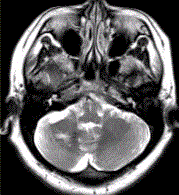

问题 患者女,41岁。头痛半年,加重10d。头部MRI显示如下图。 为进一步确定诊断,下一步的影像学检查是

选项 A.MRI增强 B.FLAIR C.DWI D.MRA E.MRV F.DSA

答案 AE

解析 AE